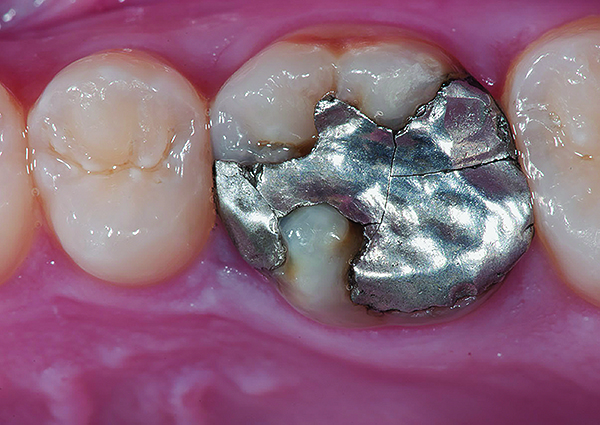

Figure 9 Preoperative preparation with composite block-out restoration, final cementation of Class IIb material, and final ceramic contour and stain by Steve Lee, CDT, MDC.

Figure 9

Figure 10 Preoperative preparation with composite block-out restoration, final cementation of Class IIb material, and final ceramic contour and stain by Steve Lee, CDT, MDC.

Figure 10

Figure 11 Preoperative preparation with composite block-out restoration, final cementation of Class IIb material, and final ceramic contour and stain by Steve Lee, CDT, MDC.

Figure 11